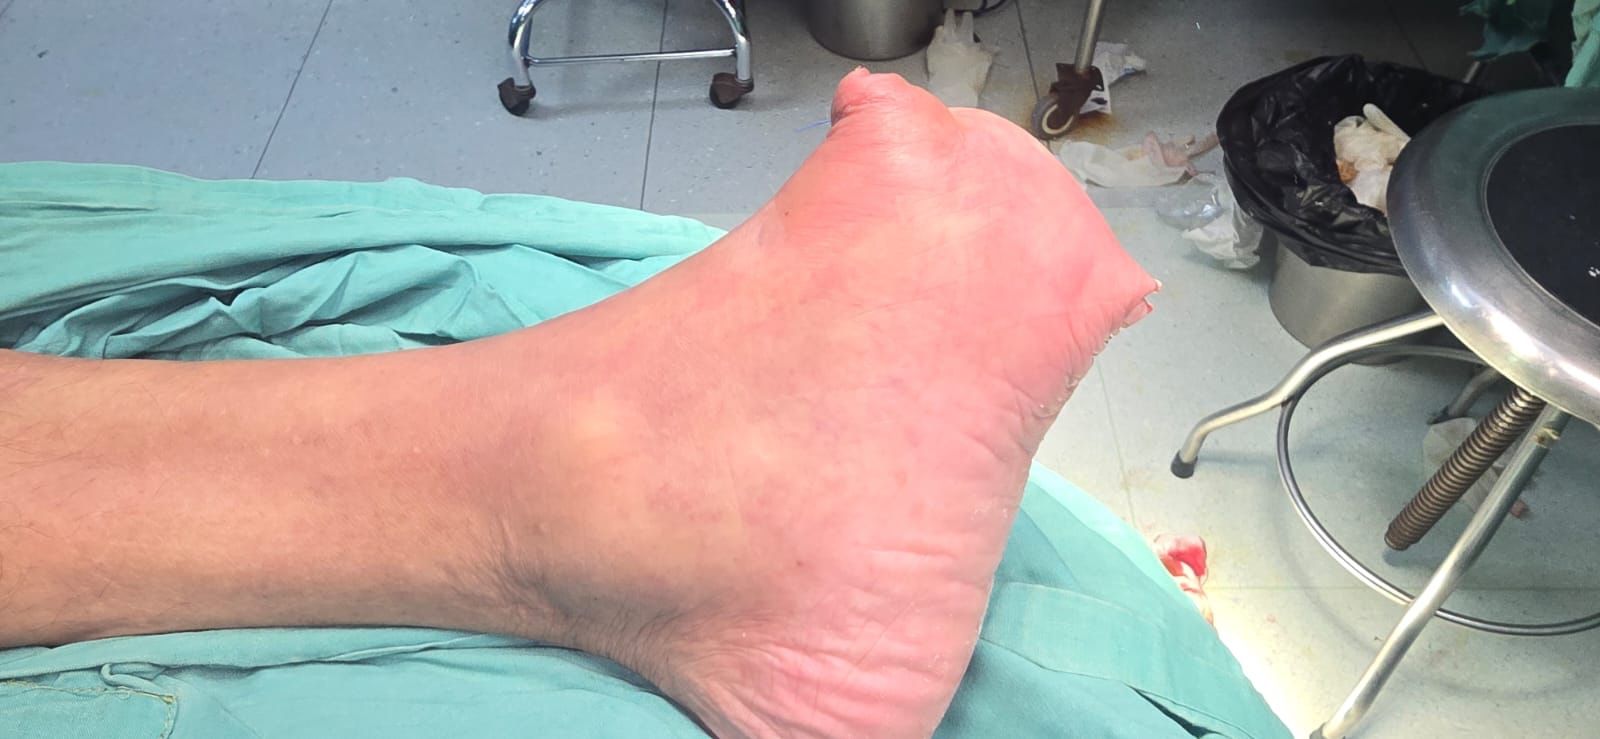

“Patient with subacute massive arterial thrombosis, documented from the distal superficial femoral artery down to the infragenicular level.

Final outcome: complete recanalization of the femoral, popliteal, and anterior tibial arteries, with restored distal flow.

A minor amputation was later performed with excellent postoperative results.”